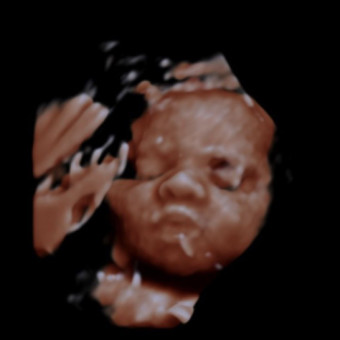

Hello! Expecting for a 2nd time, female named Samira Marie

Samira Marie